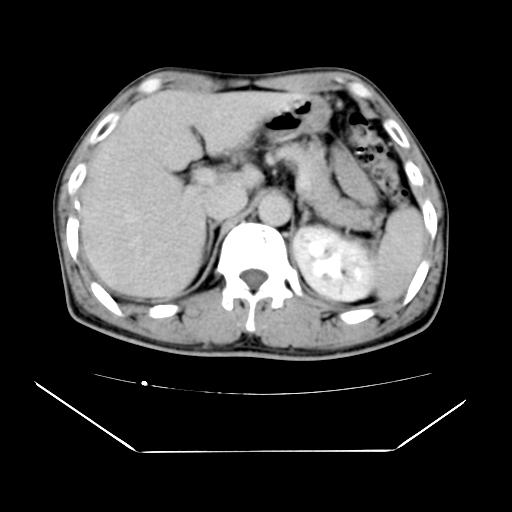

男性,55岁,外院体检afp明显升高,但b超未发现异常,否认乙肝病史。来我院ct增强。有延时扫描。

肝脏右叶动脉期可见低密度影,至延迟期被充填,考虑血管瘤可能性大。

肝右叶病灶

不排除肝右叶肝癌可能。

如果这个是癌灶的话则下腔静脉有瘤栓可能

肝6段血管瘤

血管瘤可能性大。

考虑肝右静脉影。